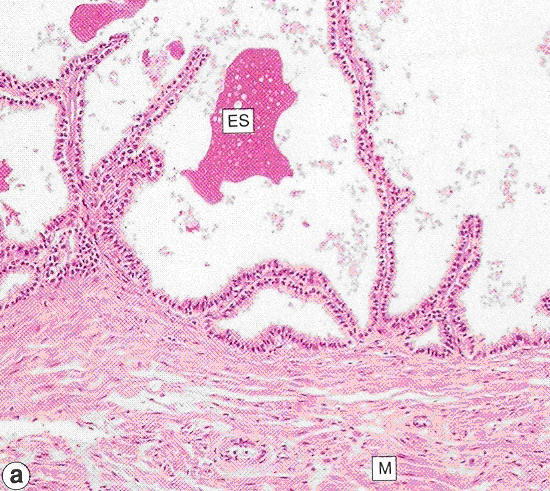

Vesicula seminalis

Seminal vesicle

M: Smooth muscle

ES: Eosinophilic secretion

Source: Stevens and Lowe Figure 17.14 (p. 315)